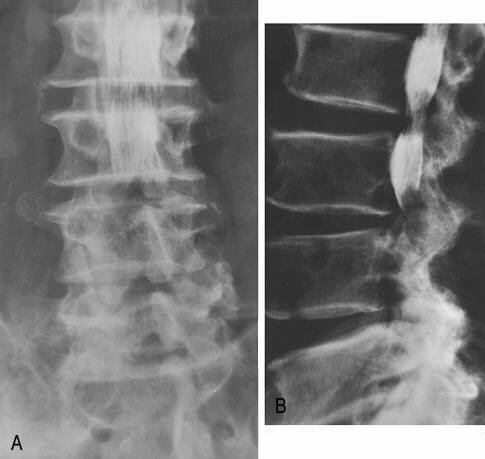

(1)腰椎管狭窄症的X线表现

在标准退行性椎管狭窄患者的侧位X线片上,可显是脊椎生理曲度减少或变直、多节段椎间隙狭窄、不稳定、关节突增生等现象的存在。